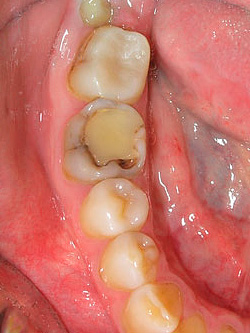

In rari casi, l'area interessata si espande verso le aree adiacenti di smalto e con uno sguardo più attento al dente si notano macchie scure. La foto sotto mostra un esempio di tale carie nascosta sotto un vecchio sigillo: